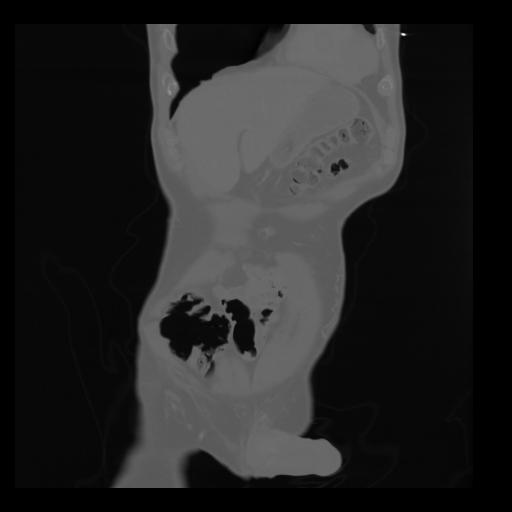

35 CUERPO,CE,Coronal,3.000,CUERPO,Coronal,